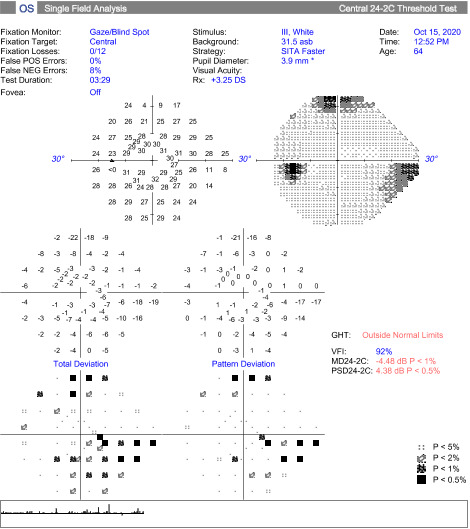

At the follow up, the patient’s vision remained stable without glasses, 20/20-1 OD and 20/25-1 OS. Humphrey Visual Field, Optos, Optos with autoflourescence, repeat B Scan, and color plates were performed at this visit. Color vision was normal in both eyes.

At the end of this visit, a diagnosis of optic nerve head drusen was determined due to the findings on the B-Scan. A highly reflective foci was seen due to the calcification present on the optic nerve head. There was no hyperflourescence seen on the fundus autoflourescent photos, but the drusen were likely buried. A 3-month follow-up was scheduled for repeat dilated fundus exam to ensure hemorrhages were resolving and no changes to the optic nerve head or visual acuity were occurring. The patient was educated on the condition of optic nerve head drusen and its effects on visual fields and vision. He was educated to return to clinic immediately if any changes were noted before the follow-up in 3 months.

Secondary complications can occur with disc drusen, but typically patients remain asymptomatic throughout life. Visual field defects are common in 24-87% of adults and up to 75% of cases and can progress with time, but patients do not normally notice the field loss.1 If a field defect is present, it is displayed as either an arcuate pattern, peripheral constriction, or an enlarged blind spot. The inferior nasal and inferior temporal quadrants are the most common arcuate defect location due to the compression of the optic nerve head fibers causing axonal loss. Visual field loss is most common in eyes with superficial drusen. As the disc drusen increase and become more exposed with time, there is a direct relationship with loss of field. Lee and Zimmerman reported a 1.6% per year increase of field loss throughout a 36-month period.6 Papilledema may produce and enlarged blind spot or visual blurring.